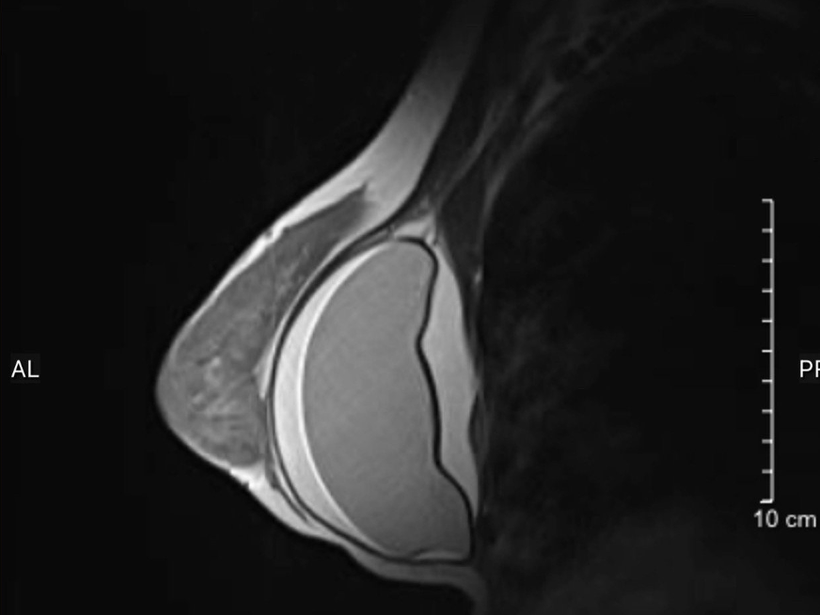

Hình ảnh chụp MRI ngực của một bệnh nhân tại Bệnh viện Đại học Y Hà Nội. (Ảnh: BVCC)

Ngày 22/4, bệnh nhân tới Bệnh viện Đại học Y Hà Nội thăm khám tổng quát. Kết quả siêu âm cũng như chụp MRI cho thấy hình ảnh túi ngực bên trái đã vỡ. Trước đó, bệnh nhân chưa nhận thấy dấu hiệu bất thường nên không hay biết túi ngực đã vỡ từ trước.

Trường hợp thứ hai là nữ bệnh nhân 31 tuổi, quê Hà Nam. Người phụ nữ mới đặt túi ngực cách đây 4 năm, đi khám do thấy vùng ngực trái căng tức, biến dạng so với bên phải. Các kết quả siêu âm, chụp MRI ghi nhận túi ngực bên trái của bệnh nhân bị vỡ, vùng khoang ngực xung quanh túi ngực có nhiều dịch (dày khoảng 2cm).